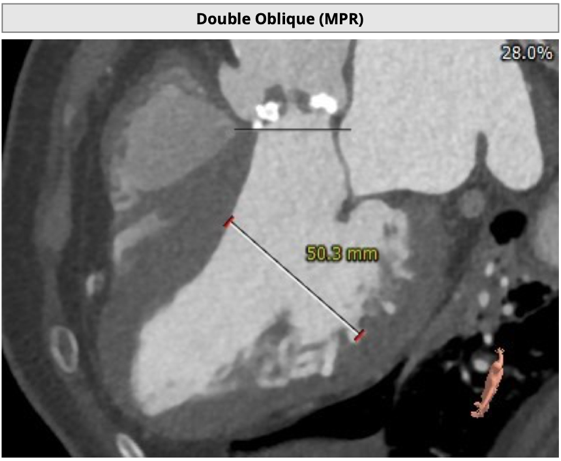

主动脉根部评估

CT 数据显示该患者为Type1型二叶式主动脉瓣

主动脉瓣瓣环周长76.8mm,周长径24.5mm;

LVOT 周长 86.1mm,周长径27.4mm;

SOV:32.3mm*34.5mm*33.7mm;

STJ 周长 100.6mm;

瓣叶严重粘连增厚,瓣叶钙化明显,HU850:1448.3mm³。

左冠开口高度8.6mm,右冠开口高度15.0mm,左冠高度偏低,左冠瓣瓣尖钙化明显,根据瓦氏窦内径和瓣叶长度综合判断,左冠存在较高堵塞风险;左心室后壁增厚。